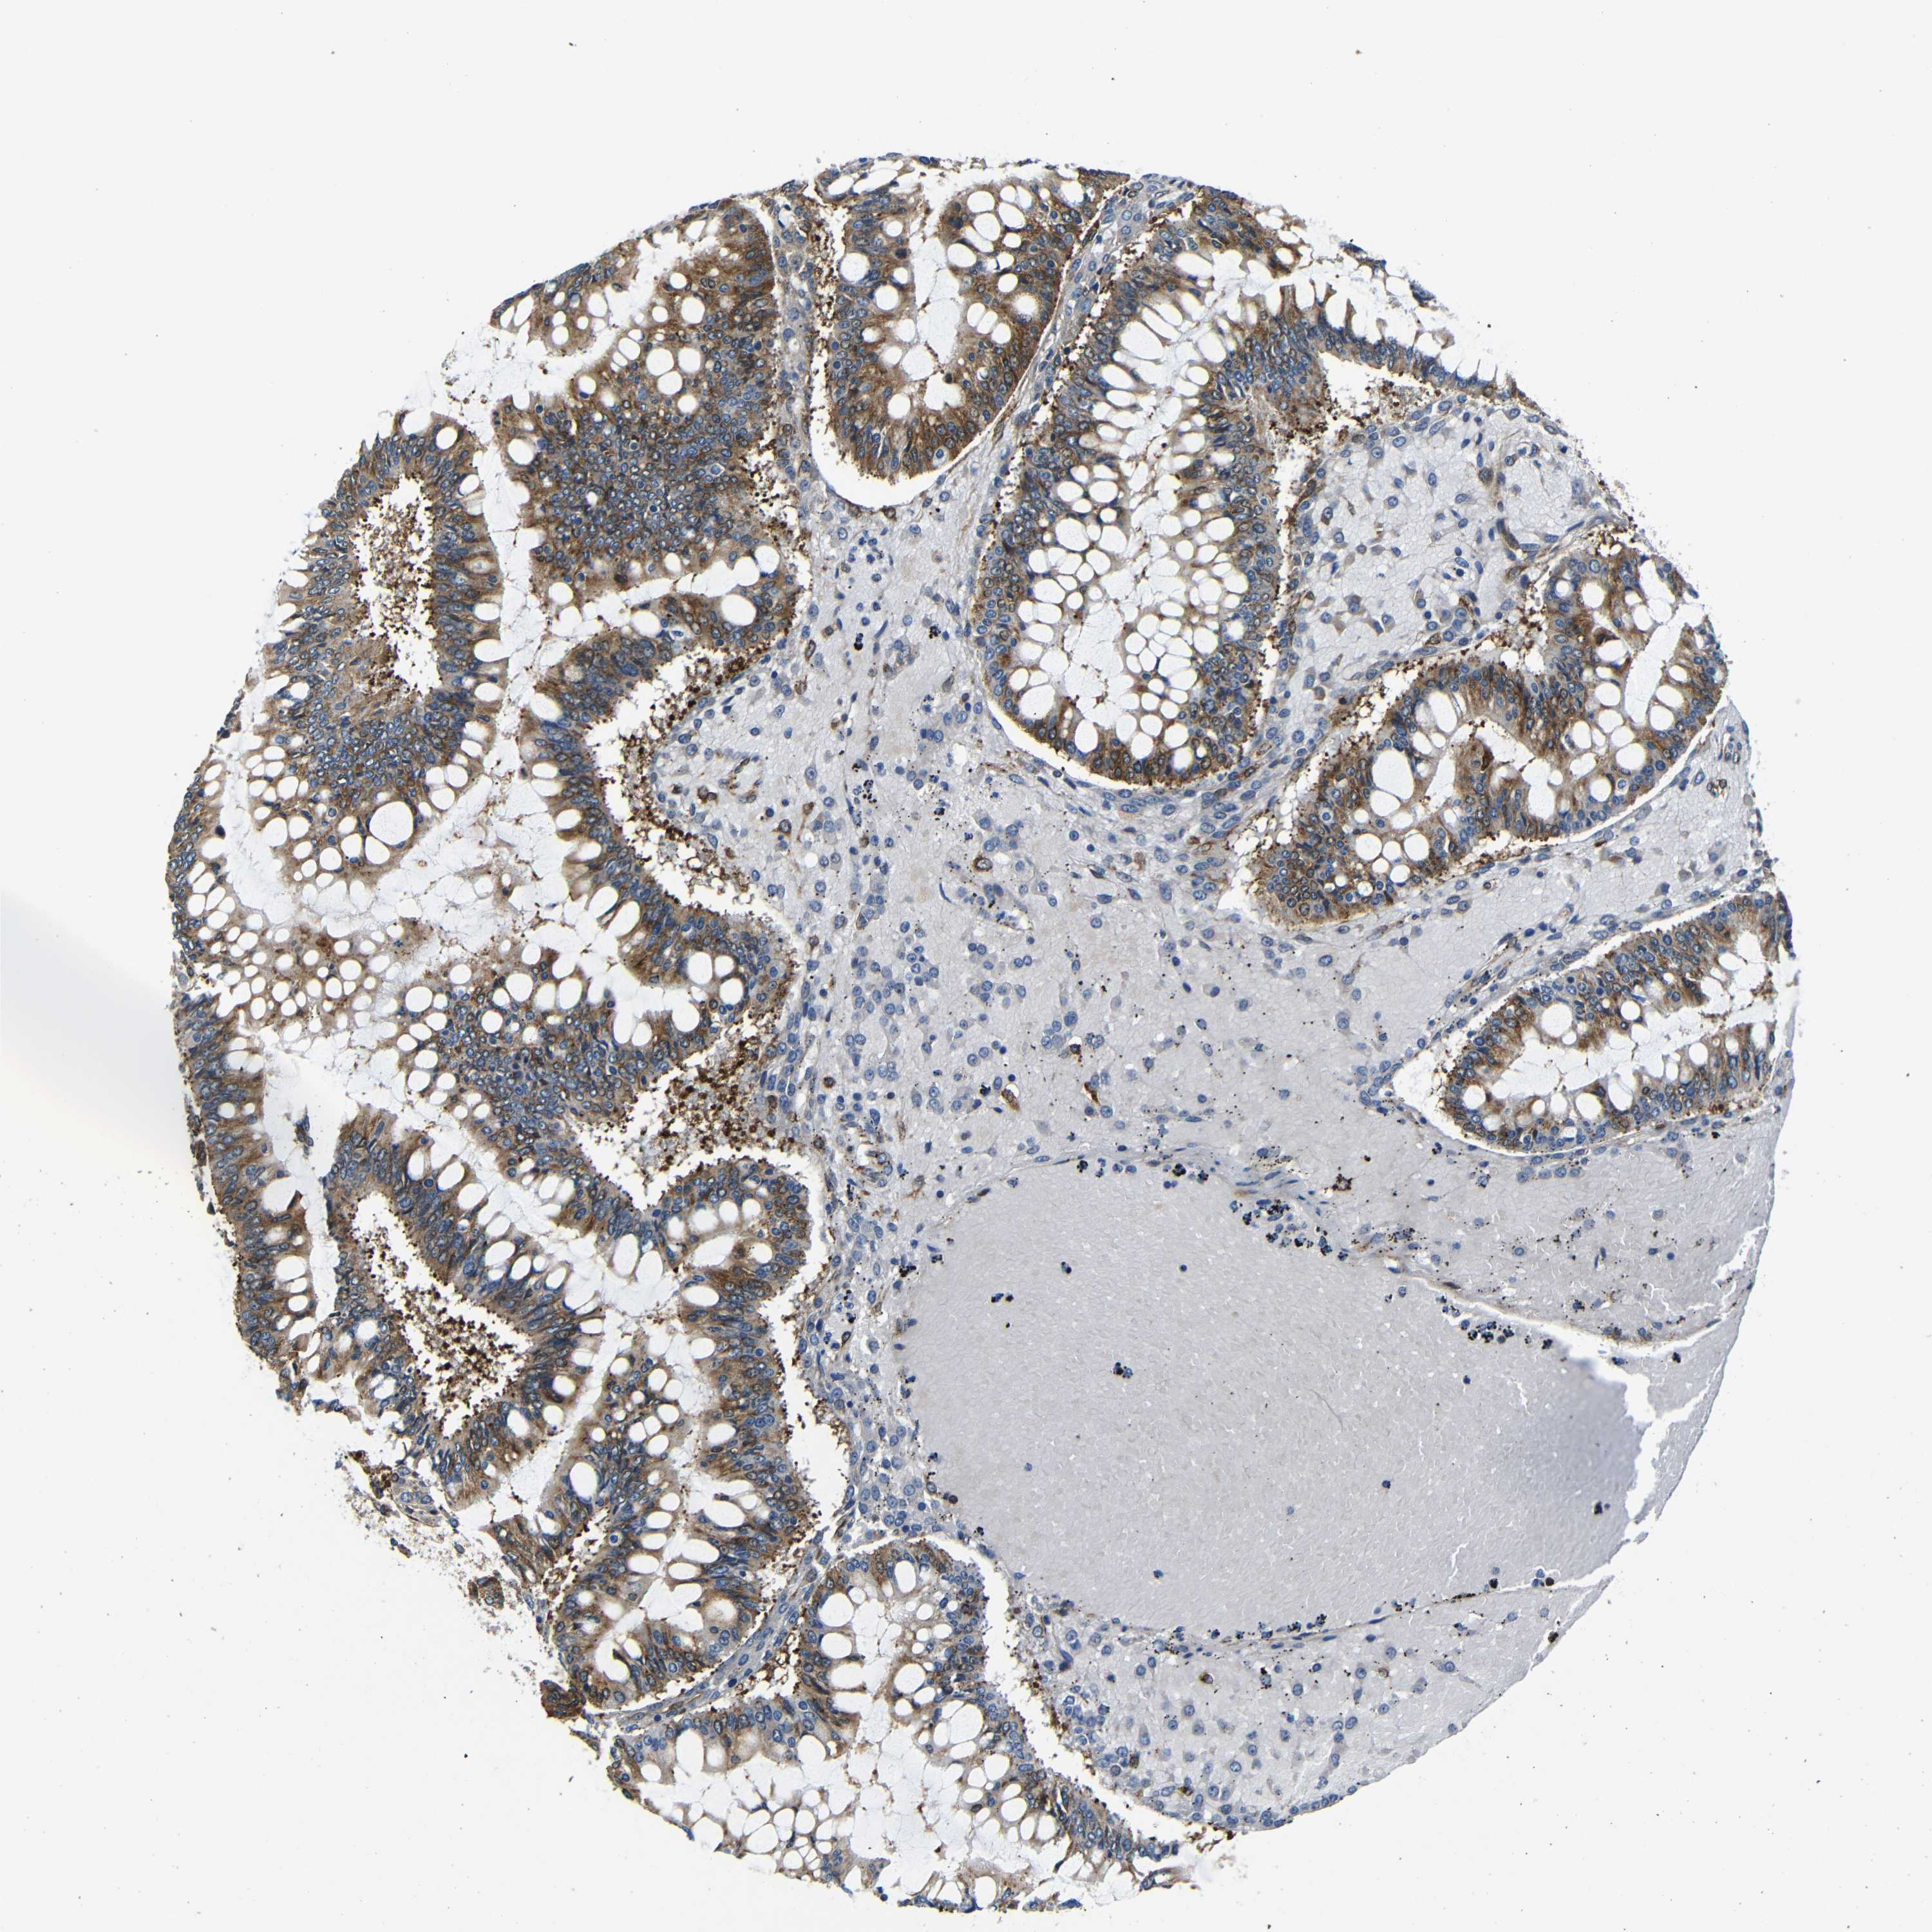

OVARIAN CANCER - Protein expressioni

A mouse-over function shows sample information and annotation data. Click on an image to view it in a full screen mode. Samples can be filtered based on level of antibody staining by selecting one or several of the following categories: high, medium, low and not detected. The assay and annotation is described here.

Note that samples used for immunohistochemistry by the Human Protein Atlas do not correspond to samples in the TCGA dataset.

Antibody stainingi

Antibody staining in the annotated cell types in the current human tissue is reported as not detected, low, medium, or high, based on conventional immunohistochemistry profiling in selected tissues. This score is based on the combination of the staining intensity and fraction of stained cells.

Each image is clickable and will lead to virtual microscopy that enables deeper exploration of all samples and also displays staining intensity scores, fraction scores and subcellular localization as well as patient and tissue information for each sample.

Antibody CAB012476

Staining

High

Medium

Low

Not detected

Intensity

Strong

Moderate

Weak

Negative

Quantity

>75%

75%-25%

<25%

None

Location

Nuclear

Cytoplasmic/membranous

Cytoplasmic/membranous,nuclear

Cystadenocarcinoma, serous, NOS

Carcinoma, endometroid

Cystadenocarcinoma, mucinous, NOS

Carcinoma, NOS